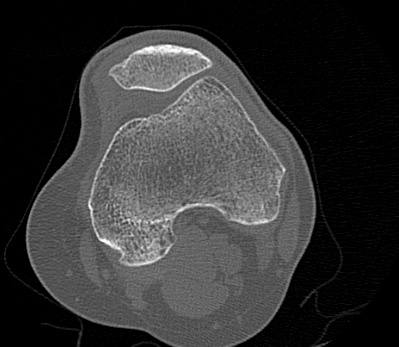

Одним из наиболее информативных методов исследования коленных суставов является мультиспиральная компьютерная томография. КТ относится к лучевым методам исследования и основана на применении ионизирующего излучения с последующей цифровой обработкой данных, полученных при КТ-сканировании.

В наших медицинских центрах обследование коленного сустава проводится на современных мультиспиральных компьютерных томографах последнего поколения TOSHIBA AQUILION. При помощи рентгеновских лучей аппараты послойно сканируют в разных плоскостях исследуемую область с толщиной среза от 0,5 мм. В результате получаются детальные снимки и цифровые трехмерные изображения коленного сустава в мельчайших подробностях. Помимо точности и достоверности диагностики современные компьютерные томографы обеспечивают для пациента минимальную дозу рентгеновского облучения.

Мультиспиральная компьютерная томография дает возможность оценить структуру костной ткани, выявить переломы, воспалительные изменения, участки деструкции костей и диагностировать опухолевые образования. Мультиспиральная КТ часто применяется в ортопедии и травматологии. За счет быстроты, доступности и неинвазивности (то есть обследование выполняется без вмешательства в организм) метод незаменим при травмах сустава, а также при планировании оперативных вмешательств, например, в случае эндопротезирования сустава. В послеоперационном периоде КТ помогает оценить эффективность проведенной операции, вовремя выявить осложнения и отследить процесс восстановления.

Что показывает КТ коленного сустава

- переломы костей;

- артроз;

- артрит;

- скопление жидкости в суставе;

- кисту Бейкера;

- костные наросты на поверхности сустава;

- новообразования

- полные или неполные вывихи — по смещению образующих сустав элементов относительно друг друга;

- деформирующий остеоартроз, ревматический полиартрит

- злокачественную или доброкачественную опухоль

- гемартроз

- абсцесс.